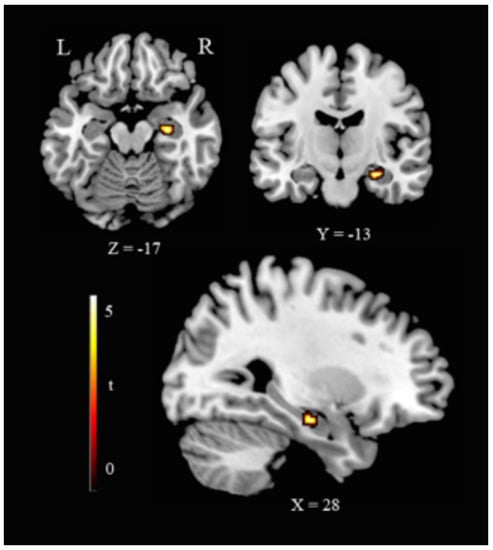

WMH+ showed lower right hippocampus volume (cluster size 81 voxels, MNI coordinates: x = 28, y = −13, z = −17; t = 4.12, equivalent Z = 3.84, p (FWE corrected) = 0.019) (Figure 2).

Figure 2.

Hippocampal volume reduction in HC(WMH+). Representative slices showing VBM ROI-based results as for the contrast HC(WMH−) > HC(WMH+). Legend: R, right; L, left; Coordinates are in Montreal Neurological Institute (MNI) space.